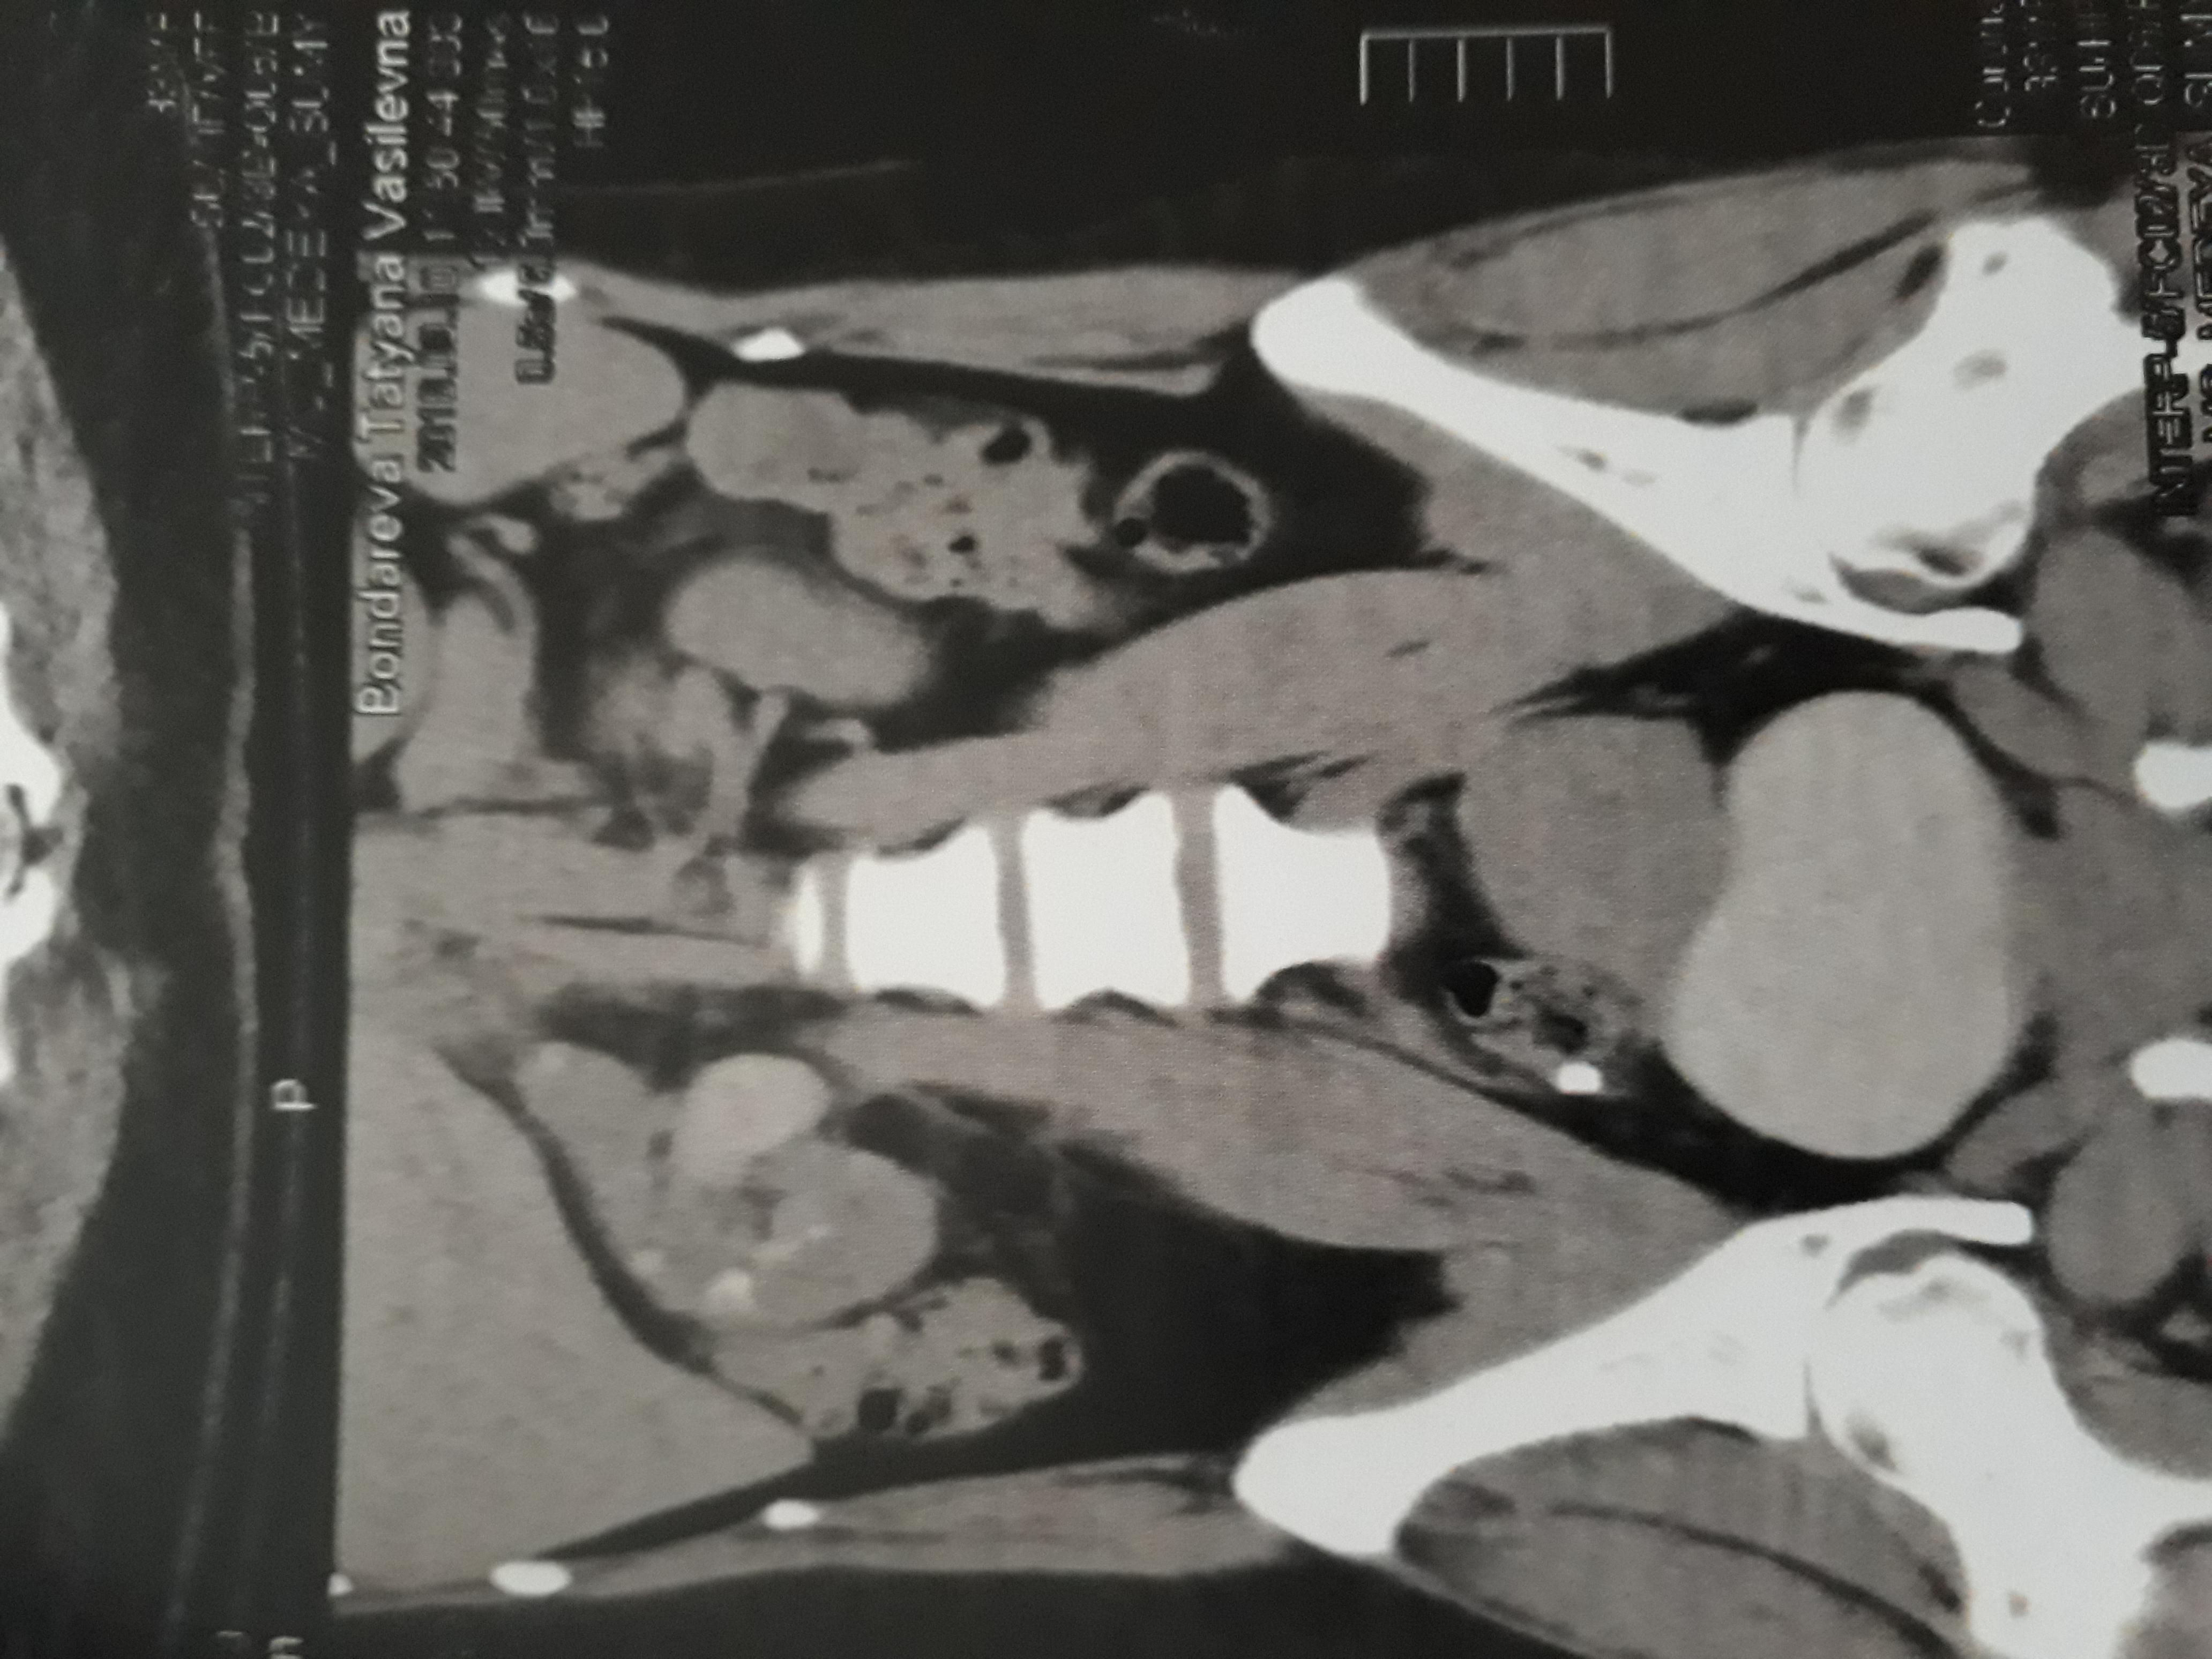

Кт исследование показало камень в мочеточнике в тазовом отделе размером 9×7×5мм.

Врач говорит надо доставать эндоскопически.Может ли он сам выйти?

Добрый день. Шанс самостоятельного отхождения камня есть, но небольшой. И чем дольше он стоит в мочеточнике, тем больше отек стенки мочеточника, тем меньше возможность его отхождения. Поэтому, возможно, Ваш врач прав. Операция занимает 15-20 минут. Удачи.